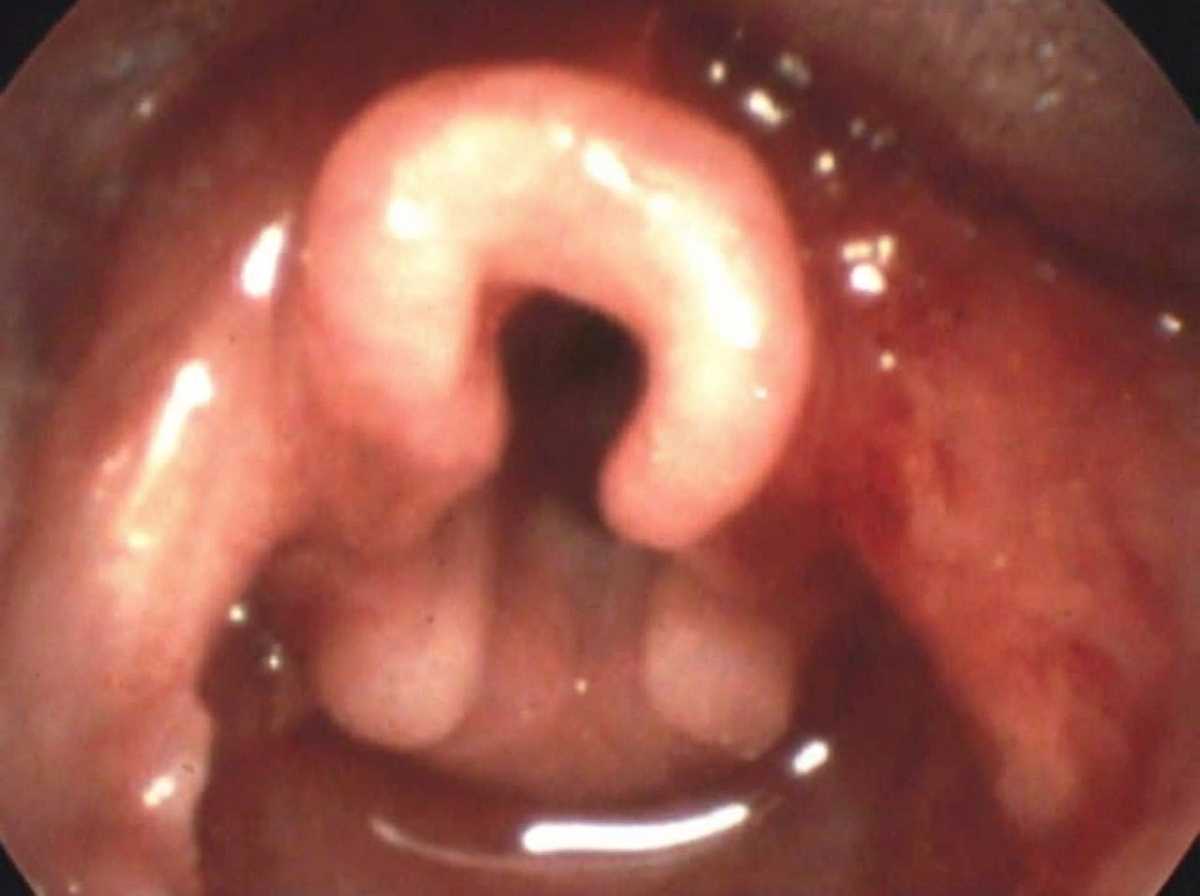

Which of the following is incorrect about the clinical condition shown below?

Explanation: ***Nocturnal cyanosis*** - **Nocturnal cyanosis is NOT a typical feature of laryngomalacia**, making this the correct answer to what is incorrect about the condition. Laryngomalacia is characterized by inspiratory stridor due to collapse of supraglottic structures, but it rarely causes cyanosis. - While symptoms may worsen during sleep, frank cyanosis indicates severe obstruction or hypoxemia, which is uncommon in typical laryngomalacia. If present, it suggests severe disease requiring surgical intervention. - Most cases of laryngomalacia are mild and self-limiting without significant oxygen desaturation. *Drooling of saliva* - Drooling is also not a typical feature of laryngomalacia, as the condition involves upper airway collapse, not difficulty with saliva management or swallowing. - However, **nocturnal cyanosis is the better answer** as it more clearly represents an atypical/severe presentation, whereas drooling is simply not associated with the condition at all. *Inspiratory stridor* - **Inspiratory stridor is the hallmark symptom** of laryngomalacia, caused by collapse of supraglottic structures during inspiration, leading to turbulent airflow. - This symptom is typically exacerbated by feeding, crying, agitation, or lying supine, and usually appears within the first 2 weeks to 2 months of life. *Omega-shaped epiglottis* - An **omega-shaped (Ω-shaped) epiglottis is a classic laryngoscopic finding** in laryngomalacia, visible during flexible laryngoscopy. - This anatomical configuration, along with redundant arytenoid mucosa and shortened aryepiglottic folds, contributes to the dynamic collapse during inspiration that causes stridor.